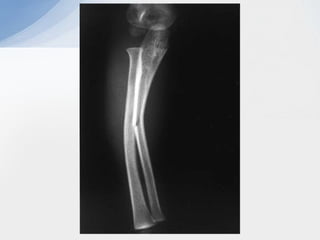

• #5 Plastic deformation of radius + greenstick of ulna